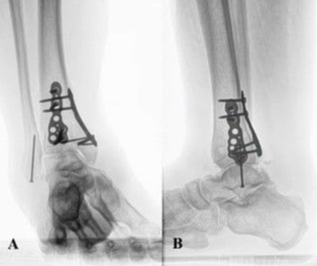

Eight months after surgery (Figure 4), the patient attended physical therapy twice weekly for 5 weeks. He reported no pain, no wound drainage, and lessening lymphedema. On examination, his lower extremity reflexes, sensation, and strength were symmetrical and intact. There was no pain with range of motion and no point tenderness, and the range of motion was excellent at 15 degrees for dorsiflexion and 25 to 30 degrees for plantar flexion. The patient ambulated without pain or discomfort but had a slightly antalgic gait secondary to immobility for an extended period.